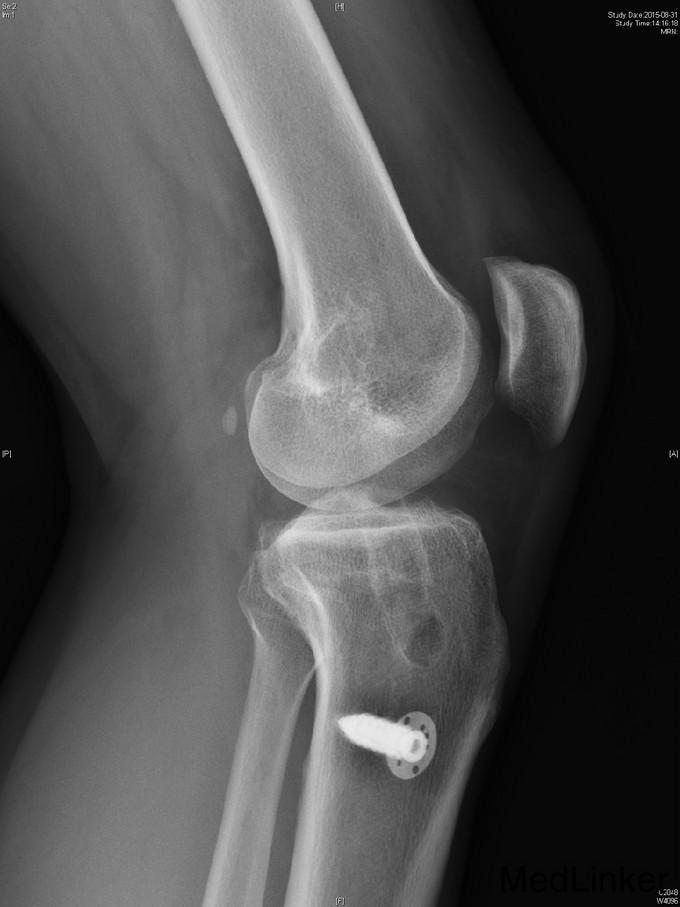

主诉:左膝前交叉韧带重建术后,要求取内固定 。 现病史:患者9年前运动时扭伤左膝关节,后出现左膝不稳、左下肢乏力。患者当时来我院就诊,诊断左膝前交叉韧带损伤,行左膝前交叉韧带自体重建术。患者自觉术后恢复良好,未规律行康复锻炼。2年前患者自觉左膝行走时偶有交锁伴疼痛。今患者为取左下肢内固定物来我院就诊。

查体:右下肢、双上肢肌力及活动度正常。左股四头肌萎缩,肌力V-级。左膝关节无明显肿胀,关节ROM尚正常,关节过伸过屈时无疼痛。髌骨活动度正常,髌周无压痛。浮髌试验(-),压磨髌(-)。麦氏征(+)。关节间隙压痛(+)。ADT(+-),Lachman征(+-),侧方应力实验(-)。双下肢无明显感觉异常。 左膝X线示:左膝术后改变。 注:患者因体内内固定无法进行核磁共振检查,这也是患者强烈要求取出内固定的原因。

诊断:左膝前交叉韧带重建术后,左膝半月板损伤。 治疗:左膝内固定取出术+左膝关节镜下探查+左膝前交叉韧带皱缩+内侧半月板成形术